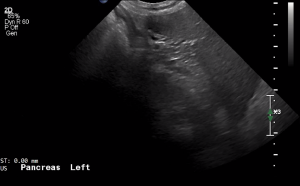

SIMON Ultrasound Database

This ultrasound database is a free resource for students and doctors!

Our collection includes videos of dogs, cats, horses, cows, humans, and many other species!

–Canine and Feline abdominal ultrasound videos were generously provided by the Cummings School of Veterinary Medicine at Tufts University.